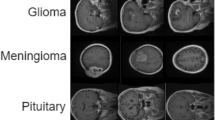

Generative Adversarial Networks (GANs) have gained significant attention in several computer vision tasks for generating high-quality synthetic data. Various medical applications including diagnostic imaging and radiation therapy can benefit greatly from synthetic data generation due to data scarcity in the domain. However, medical image data is typically kept in 3D space, and generative models suffer from the curse of dimensionality issues in generating such synthetic data. In this paper, we investigate the potential of GANs for generating connected 3D volumes. We propose an improved version of 3D α-GAN by incorporating various architectural enhancements. On a synthetic dataset of connected 3D spheres and ellipsoids, our model can generate fully connected 3D shapes with similar geometrical characteristics to that of training data. We also show that our 3D GAN model can successfully generate high-quality 3D tumor volumes and associated treatment specifications (e.g., isocenter locations). Similar moment invariants to the training data as well as fully connected 3D shapes confirm that improved 3D α-GAN implicitly learns the training data distribution, and generates realistic-looking samples. The capability of improved 3D α-GAN makes it a valuable source for generating synthetic medical image data that can help future research in this domain.

In this section, we present side-by-side illustrations of the training data and generated samples by improved α-GAN to highlight the model’s performance. Figure 23 and 24 illustrate training samples and most similar generated data samples for 3D connected and tumor volumes. Generated shapes maintain the connectivity of the voxels, but the level of the convexity is slightly reduced compared in the provided sample compared to the training data.